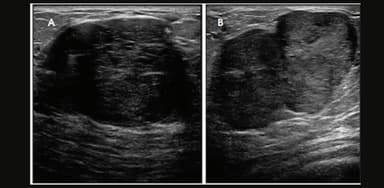

Nhân giảm âm tuyến vú BIRADS 3 được đánh giá theo hệ thống phân loại BIRADS (Breast Imaging Reporting and Data System). BI-RADS (Hệ thống dữ liệu và báo cáo hình ảnh vú) là một hệ thống phân loại tiêu chuẩn được các bác sĩ Chẩn đoán hình ảnh sử dụng để phân loại các phát hiện trong siêu âm hình ảnh vú. Hệ thống này sử dụng thang điểm từ 0 đến 6 để biểu thị mức độ nghi ngờ đối với các bất thường ở vú, với số lượng cao hơn thường cho thấy khả năng mắc bệnh ác tính (ung thư) cao hơn.

Đa số nhân tuyến vú BIRADS 3 là lành tính

Nhân giảm âm BIRADS từ 3- 6 xác suất ung thư sẽ tăng dần. Dưới đây là bảng phân loại siêu âm tuyến vú BIRADS: